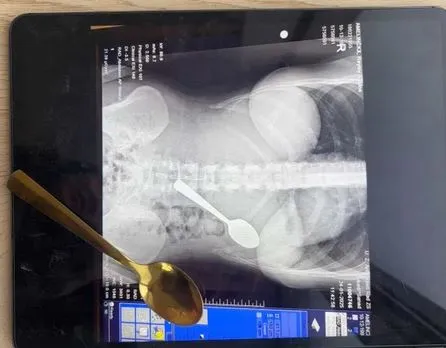

Необичаен случай в Белгия приключи със незабавна здравна интервенция. Млада жена инцидентно погълнала 17-сантиметрова лъжица, до момента в който похапвала кисело мляко вкъщи.

Лекарите открили, че лъжицата е прекомерно огромна, с цел да премине естествено през организма, и възнамерявали гастроскопия за изваждането ѝ. През нощта преди процедурата дамата усещала придвижването на предмета и изпитвала мощен дискомфорт, написа Metro.

Два дни по-късно лъжицата била сполучливо отстранена под локална анестезия. По време на процедурата лекарите трябвало да я завъртят, което предизвикало дребен стомашен кръвоизлив. Въпреки това Рейми се възстановила без трайни увреждания, въпреки да имала краткотрайно възпалено гърло и сензитивен корем.